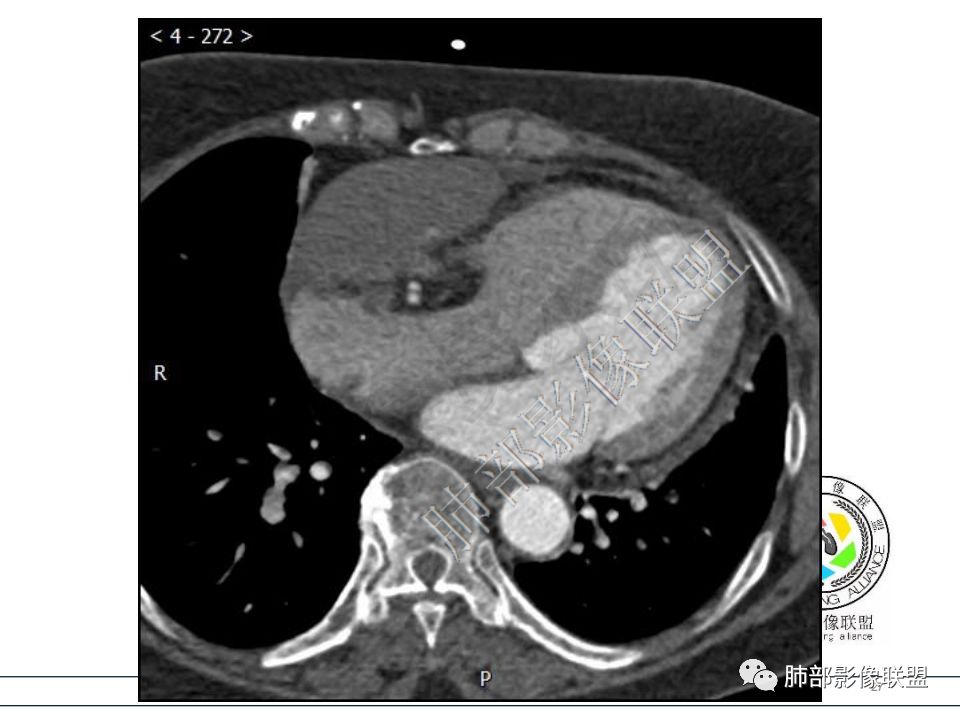

病例一考虑心包来源,病灶从大动脉根部一直延续到心底,明显不均匀强化,没有心包积液,良性?边缘强化,良性先考虑血管瘤。

病变位于心包,密度较低,边缘结节性强化,猜一个血管瘤。 医学百科网 | YxBaike.Com

定位心包,局部与右心房分界不清,右心房受压,冠脉受压,渐进性强化,没有心包积液,考虑心包来源或右心房游离壁来源血管瘤。 医学百科网 | YxBaike.Com

从心底沿右侧房室沟一直延伸至近膈面,心包来源可以解释的通;另外病变与右心室右心房之间的脂肪间隙一直存在。

心包海绵状血管瘤的CT特征为平扫呈边界清楚的圆形或者类圆形低密度肿块,对比增强扫描是诊断海绵状血管瘤的关键。动脉期肿瘤边缘可出现散在斑片状、结节状明显强化灶,接近同层强化大血管密度。静脉期散在的强化灶相互融合同时向肿瘤中央扩展。 医学百科网 | YxBaike.Com

渐进性强化,边界清晰,周围脂肪间隙存在,没有心包积液。 医学百科网 | YxBaike.Com

边界清晰,周围脂肪间隙存在,临近器官受压无受累。 医学百科网 | YxBaike.Com